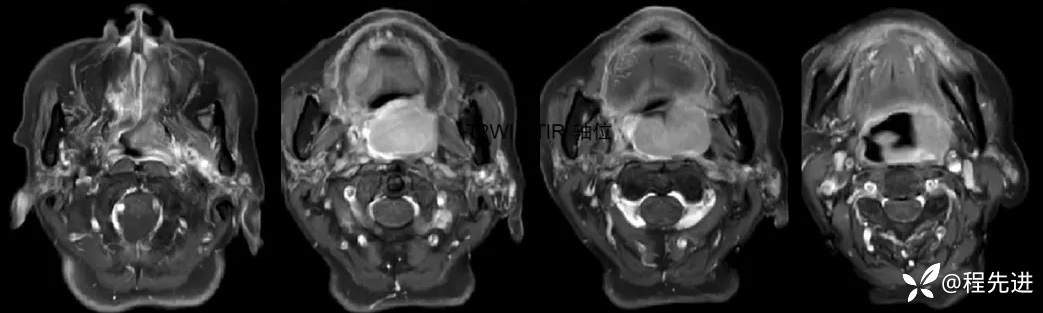

MRI平扫+增强:

T1压脂增强: